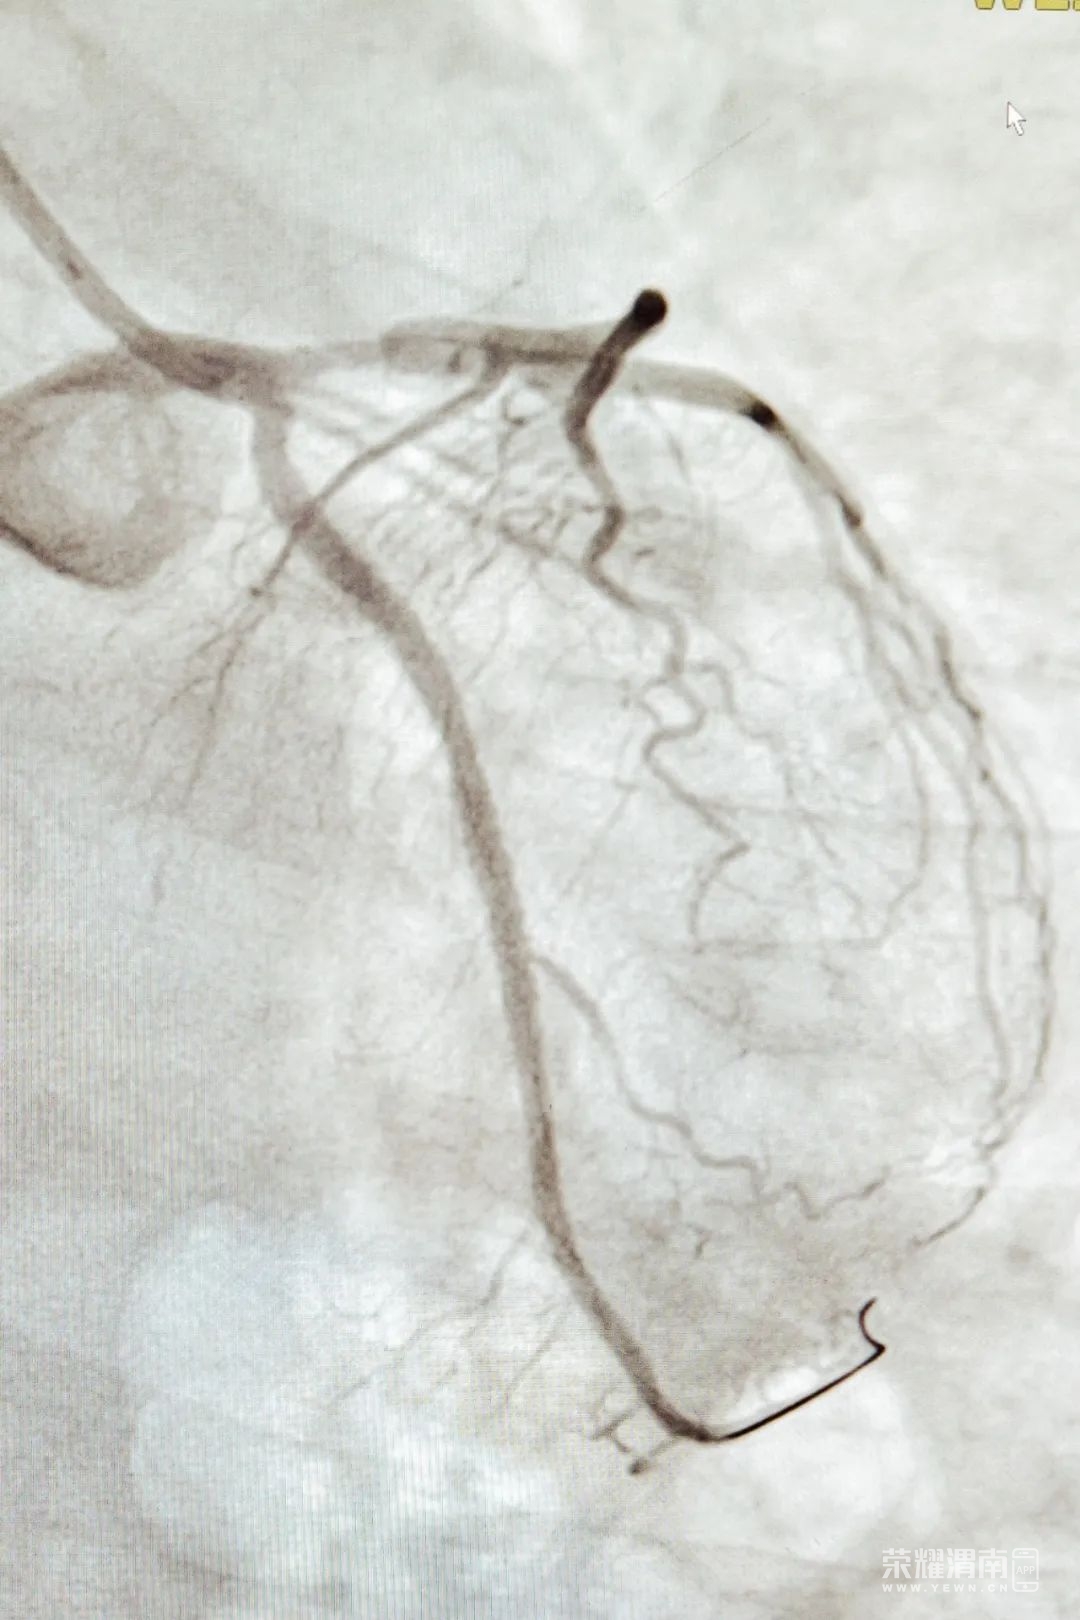

4月3日早晨9点左右,72岁的老王突然感到胸口疼痛,喘不过气来,还出了一身汗。他赶紧去了临渭区固市卫生院检查,结果显示他的心跳有点慢。另外,一种叫肌钙蛋白的东西在他的血液里浓度比较高,这通常是心肌受损的信号。医生们发现了问题,并迅速将老王送到了渭南市第一医院急诊科。在市一院,医生们再次检查了老王的心电图,发现了他心脏的问题,急性心肌梗死。血液检查结果也证实了这一点。老王的过去病史显示,他有高血压已经十年了,但一直没有好好控制血压。这次的情况让医生们特别担心。 医务科的科长姜亮立刻做出决定:启动急性心梗救治绿色通道。老王被安排做了冠脉造影检查,结果显示他的心脏血管有两处很严重的狭窄。副主任医师谢军芳主刀,赵志伟医生医生辅助,迅速采取措施,为老王进行支架植入手术。手术非常成功,老王术后的胸痛症状明显减轻,他安全地返回了病房。1.老年人心梗多为无痛性心梗,通常表现为呼吸困难,如严重胸闷、气短、心衰等,或者低血压,如突然昏倒、视力模糊、神志模糊等。2.脑循环障碍型,这类心梗征兆主要表现为头部症状,比如头晕、头痛、神志不清、意识模糊、精神萎靡等。3.心梗高危人群如果出现脐周、牙齿、肩胛骨、颈部、左前臂、左腿等即非心脏区域的疼痛,也不容忽略,需警惕是心梗的征兆。1.及时拨打120急救电话,尽快去就近有救治能力的医院。 2.把握黄金救治120分钟,时间就是生命。 1.第一关是第一时间拨打120急救电话。这是最关键的一关,有心梗危险因素的人,一旦出现胸痛胸闷等症状时,应马上停止任何活动,第一时间拨打120急救电话,原地平静等待救援。2.第二关是就近就医。120急救中心出动救护车将患者送至距离最近的具有相关救治能力的医院,特别强调,此刻不要挑医院,一定要注意就近原则。3.第三关是积极配合医院救治工作。尽量争取发病120分钟内接受再灌注治疗,即溶栓或急诊冠脉造影,必要时行支架治疗。谨记,患者及家属要充分的相信医生,配合医生的工作,时间就是心肌,不要将宝贵的时间浪费在无用的纠结中。1.注意食物多样性及低盐低脂饮食:限制钠盐摄入每日不超过6克,每天增加新鲜蔬菜、水果摄入,红肉每天摄入应低于35克,高脂血症和心血管病高危人群,胆固醇摄入应少于300mg。2.增加体育锻炼:65岁以上老年人应结合身体情况适当活动,避免久坐不动。健康成年人可保持每周2小时以上中等强度有氧活动。如不知如何评估运动能力,可前往湖南省中西医结合医院(湖南省中医药研究院附属医院)心脏康复中心制定心脏康复训练计划。3.戒烟限酒:主动戒烟,避免吸食二手烟;严格控制酒精摄入,成年男性每天少于25克,女性少于15克。4.保持情绪稳定,心情愉悦,心态平和,避免情绪激动、焦虑紧张、熬夜劳累。5.冬天注意防寒保暖,夏天避免高温暴晒,或吹空调贪凉及一冷一热的情况。1.血压:老年人血压应控制在140/90mmHg以内,高危患者可更严格的控制在130/80mmHg以内,80岁以上的老年人可适当放宽至150/90mmHg以内。用药需谨遵医嘱,不要私自调整药物品种及剂量,如有疑问可至医院心血管专科就诊,在专业医生的指导下调整药物。2.血脂:高危人群应定期于心血管专科监测血脂指标,长期坚持服用他汀类药物,如血脂不达标可在专业医生的指导下联用其他药物,如依折麦布、本院院内制剂复方血脂片、必要时可加用PCSK9抑制剂。3.血糖:老年人糖化血红蛋白应控制在6.5%以内,如果明确诊断2型糖尿病,病程长、高龄患者可维持在8%以内即可。定期监测血糖,用药遵医嘱,定期专科就诊,在专业的医生指导下调整药物及剂量。5.出现心肌梗死征兆,需立即就医,中西医结合治疗,协同增效。